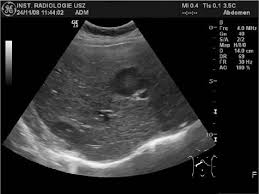

Pyogenic Abscess